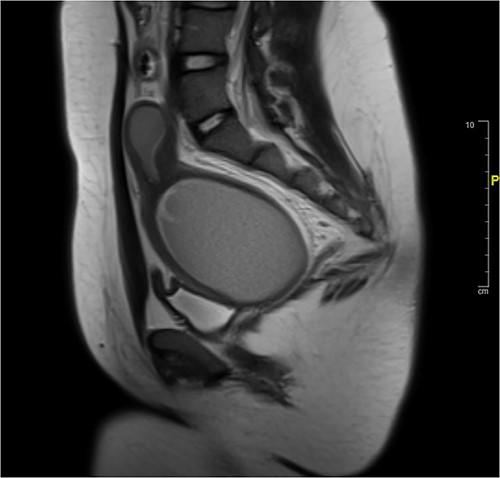

A 13-year-old female presented to the emergency department for increasingly severe chronic cyclic abdominal. She reported thelarche and pubarche at age 11 but had not reached menarche. Physical exam was significant for general abdominal tenderness and firm abdominal mass. External genitalia were notable for a normal hymen but no vaginal opening or bulge. On rectal exam, a firm mass was palpated ~4 cm proximal to anal opening. Imaging confirmed HMC with distension of the proximal vagina measuring 9.9 cm in its greatest dimension. The area of vaginal agenesis was ~5 cm from distal end of HMC to the perineum (Fig. 1).